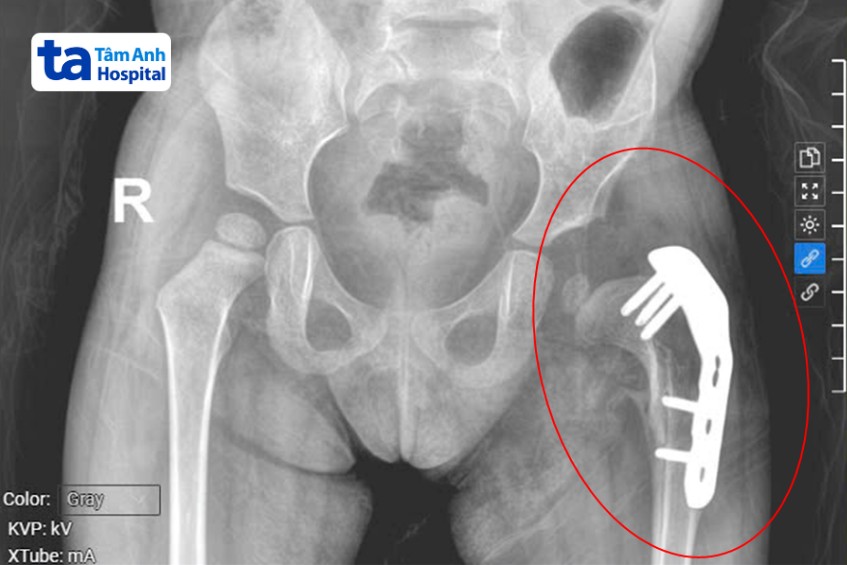

ThS.BS.CKI Tôn Thị Anh Tú, chuyên khoa Ngoại Nhi cho biết phần chỏm xương đùi bệnh nhi bị tái trật ra khỏi ổ cối (phần xương chậu), cần phẫu thuật lại lần hai để mở rộng và tạo hình lại, chỉnh trục xương đùi, nắn chỏm xương đùi vào ổ cối, sau đó dùng nẹp vít cố định lại.

Êkíp bác sĩ tiếp cận cấu trúc khớp háng bị trật, tiến hành tách cơ bám vào mào chậu, mở rộng ổ cối và đặt lại chỏm xương đùi, đưa khớp háng về đúng vị trí. Sau đó đặt nẹp vít để cố định và khâu tái tạo lại bao khớp háng, đóng vết mổ. Bé được chăm sóc hậu phẫu, xuất viện sau một tuần.

Tháng 5/2025, bé tái khám, khớp háng đã về đúng cấu trúc thông thường, bác sĩ chỉ định phẫu thuật lần thứ ba để tháo nẹp vít, kết thúc quá trình điều trị. Bác sĩ rạch một đường tại vị trí vết mổ cũ vùng bẹn, kiểm tra lại cấu trúc khớp háng bị trật, lấy dụng cụ nẹp ra và đóng lại. Bệnh nhi xuất viện sau 1 ngày.